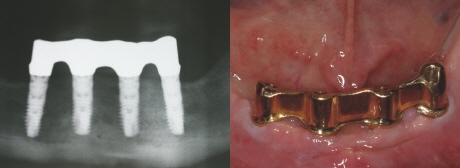

Die Versorgung

Die vier Implantate sind nun mit einem individuell gefäßten Steg aus einer Goldlegierung miteinander verbunden. Dieser Steg wird auf die einzelnen Implantate fest aufgeschraubt (Bild oben rechts). Der perfekte Sitz wird mit einm Röntgenbild kontrolliert (Bild oben links).